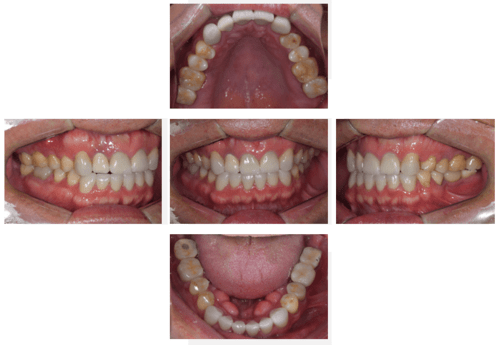

インプラント治療の症例15

レントゲン写真

- Before

- After

口腔内写真

- 途中経過-1

- 途中経過-2

| 年齢 | 40代・男性 |

|---|---|

| 主訴 | 右上1番 左上5、6、7番 |

| 治療内容 | インプラント埋入 |

| 治療費 | 合計:2,453,000円 ・内訳 インプラント診断料 55,000円 インプラント埋入料 165,000円×4 サージカルガイド 88,000円 サイナスリフト 220,000円 GBR 110,000円 FGG 110,000円 2次オペ 22,000円×4 インプラント仮歯 55,000円×4 インプラント上部構造 187,000×4 静脈内鎮静法 77,000×2 (2024年6月現在) |

| 治療期間 | 1年1ヶ月 |

| 治療方針 | 右上の1番は20年以上前に前装冠を入れた所が半分折れていました。 もともと4本とも根管治療していた歯で再感染しており残すのが難しかったため抜歯を行いました。 左上567は骨造成とインプラント埋入を同時に行いました。 左上1番は骨造成を行ってから4ヶ月骨が出来るまでまってからインプラントを埋入しました。 |

| 特記事項 | インプラントは人工物なので虫歯になることはありませんが、歯周病(インプラント周囲炎)にはなります。 インプラントを長持ちさせるには、毎日の歯磨きと合わせて3~6ヶ月ごとの定期検診でのクリーニングが大切です。 |

| 担当者所見 | 右上の1番は歯ぐきの足りない部分に健康な歯ぐきを移植する外科手術を行いました。 手術後自然な歯ぐきが再現されました。 オープンバイトのため奥歯に負担がかかっており治療後はマウスピースを使用するよう指導しました。 |